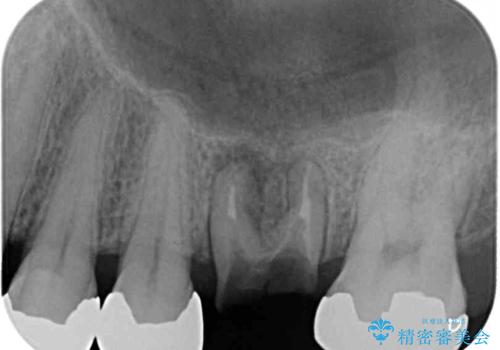

- 根っこの一部だけになった歯と咬むと痛みのある歯を気にして来院された患者様です。

上顎の歯根のみとなった歯は抜歯が必要であったので、抜歯を行い、インプラントあるいはブリッジのよる補綴治療を提案しました。

下顎の根管治療がされた大臼歯は咬合時に痛みが認められたため、再度根管治療を行った後に補綴治療することとしました。

歯根のみとなっていた上顎の歯は、そのうち治療すれば残せるであろうと思っていたようですが、どこの歯医者に相談しても抜歯と言われたため、抜歯することとしたようです。